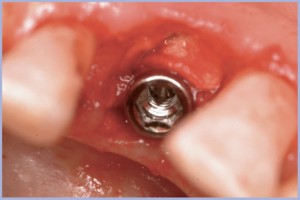

- Figg. 19, 20 – Rimozione del tappo basso con connessione conica dopo circa 6 mesi

- Fig. 20

- Fig. 21 – Inserimento di un moncone preinclinato a 15°